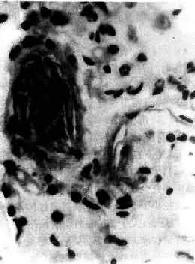

图3-9 肺羊水栓塞 小血管内有角化上皮 (五)其他栓塞 肿瘤细胞栓塞,可引起肿瘤在局部形成转移瘤(图3-10)。寄生虫、虫卵和其他异物偶可进入血循环引起栓塞。